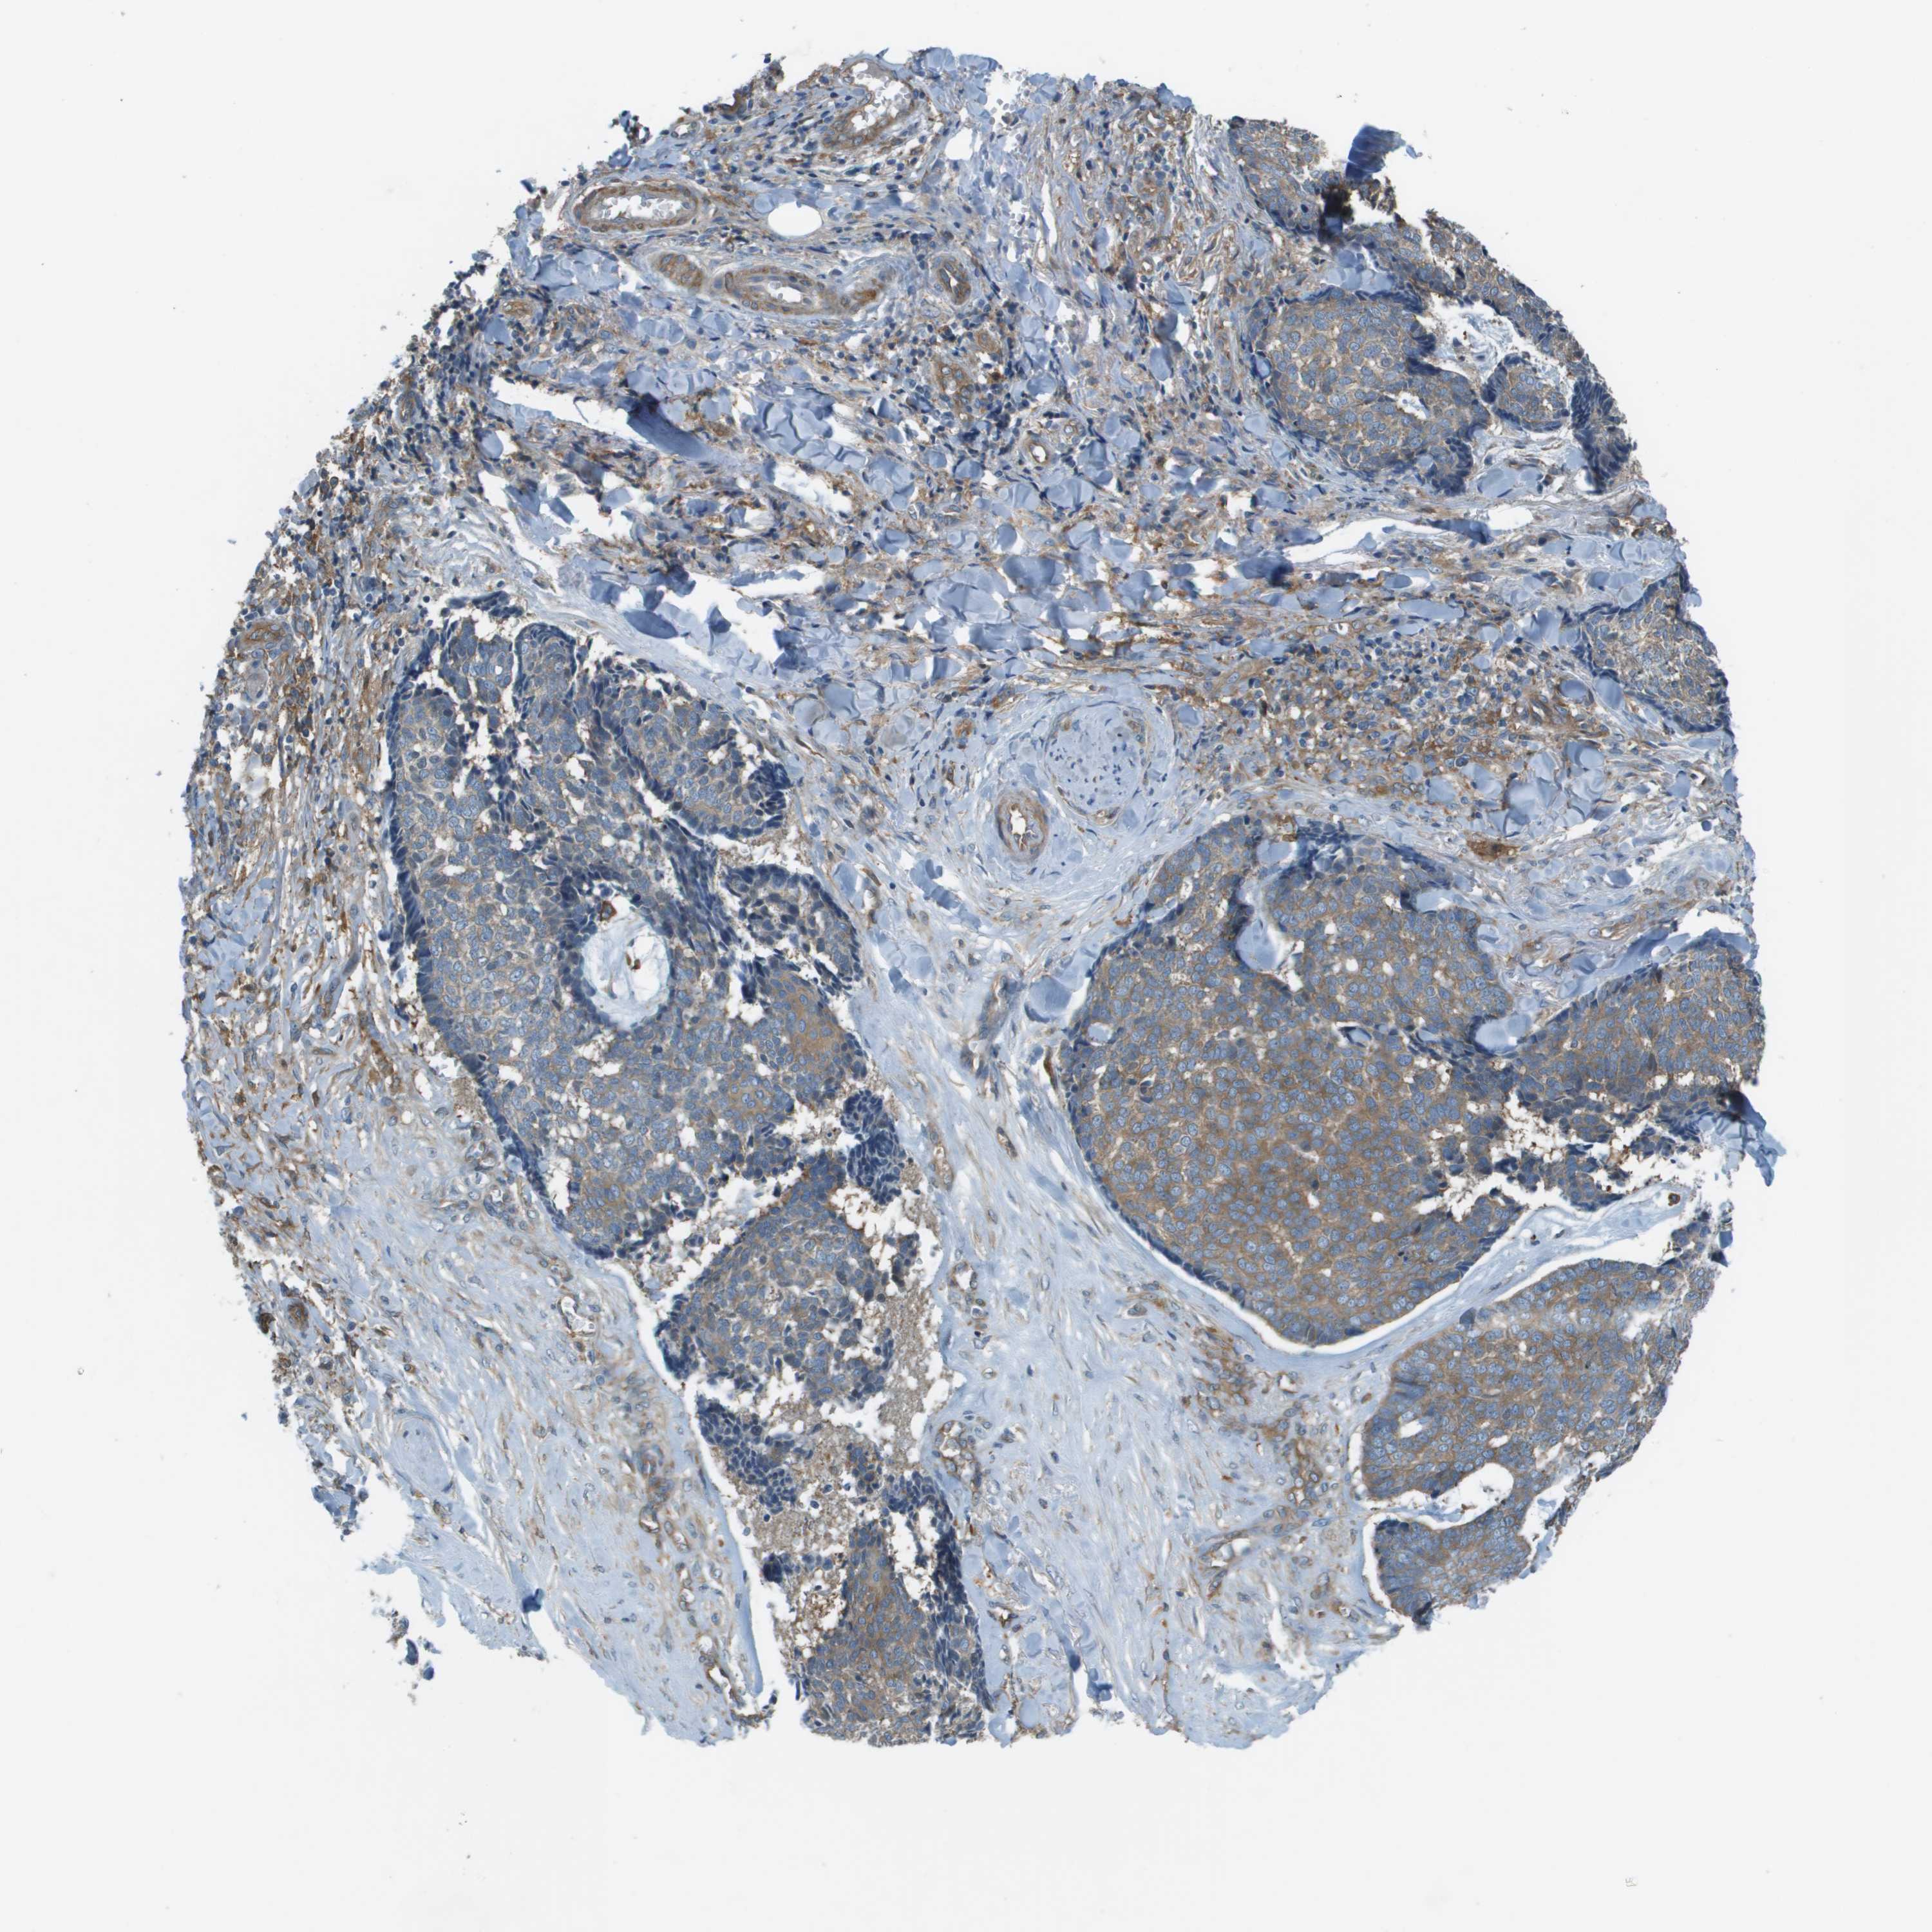

SKIN CANCER - Protein expressioni

A mouse-over function shows sample information and annotation data. Click on an image to view it in a full screen mode. Samples can be filtered based on level of antibody staining by selecting one or several of the following categories: high, medium, low and not detected. The assay and annotation is described here.

Antibody stainingi

Antibody staining in the annotated cell types in the current human tissue is reported as not detected, low, medium, or high, based on conventional immunohistochemistry profiling in selected tissues. This score is based on the combination of the staining intensity and fraction of stained cells.

Each image is clickable and will lead to virtual microscopy that enables deeper exploration of all samples and also displays staining intensity scores, fraction scores and subcellular localization as well as patient and tissue information for each sample.

Antibody HPA070456

Antibody CAB017616

Staining

High

Medium

Low

Not detected

Intensity

Strong

Moderate

Weak

Negative

Quantity

>75%

75%-25%

<25%

None

Location

Nuclear

Cytoplasmic/membranous

Cytoplasmic/membranous,nuclear

Basal cell carcinoma

Squamous cell carcinoma, NOS

Squamous cell carcinoma in situ, NOS

Adnexal tumor, benign